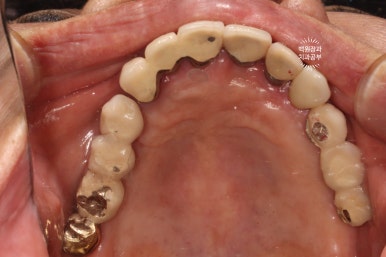

좌측은 위턱 사진, 오른쪽은 아래턱 구강내 사진입니다.

아주 어렵지 않게 두 치아가 부러져 있다는 것을 확인할 수 있죠.

위턱의 씹는면을 보시면, 스트라우만 임플란트로 아주 깔끔히 치료된 것을 보실 수 있습니다.

옛날에 치료받았던 스트라우만 임플란트는 이제 오래되어... 조금 깨지도 닳은 것은 보이나, 사실 기능하는데는 문제가 없었어요. 20년이 넘었음에도 이렇게 훌륭한 임상결과를 보이는 스트라우만 임플란트. 정말 최고임을 직접 보여주고 있었습니다. 진짜 올타임 넘버원 임플란트입니다.